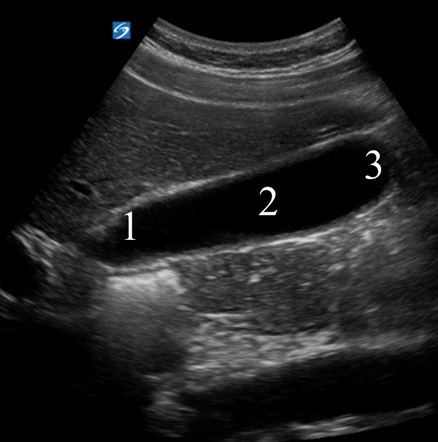

Gallbladder Anatomy Image

Neck

Body

Fundus